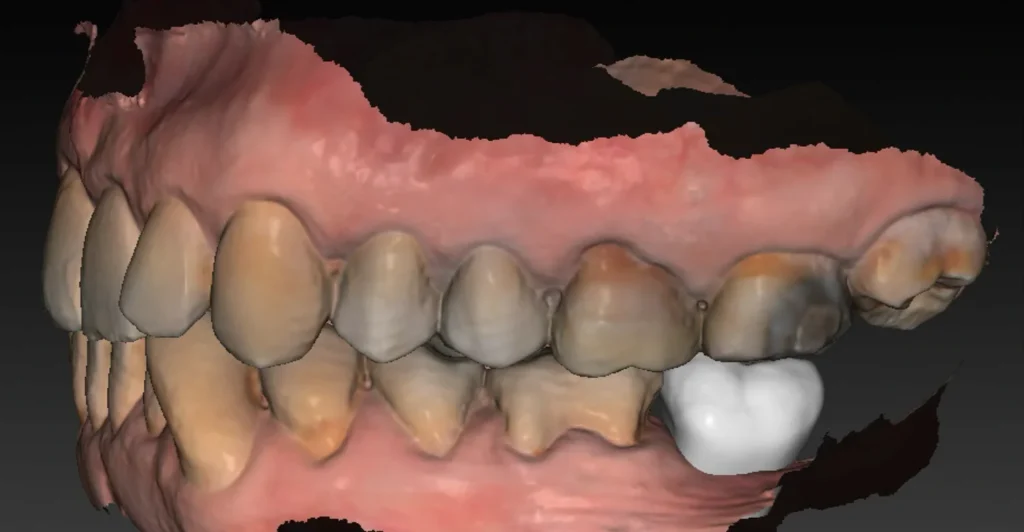

Une empreinte optique est également effectuée. Elle permet :

- de visualiser avec précision le relief gingival et d’identifier les zones nécessitant éventuellement une greffe de gencive ;

- d’évaluer les rapports occlusaux en vue de la future restauration prothétique ;

- d’alimenter la planification numérique en superposant les données optiques au volume osseux issu du Cone Beam.

L’ensemble de ces données permet ensuite de réaliser une planification implantaire précise, fondée sur une analyse tridimensionnelle croisée des tissus durs et mous, et tenant compte des exigences prothétiques.